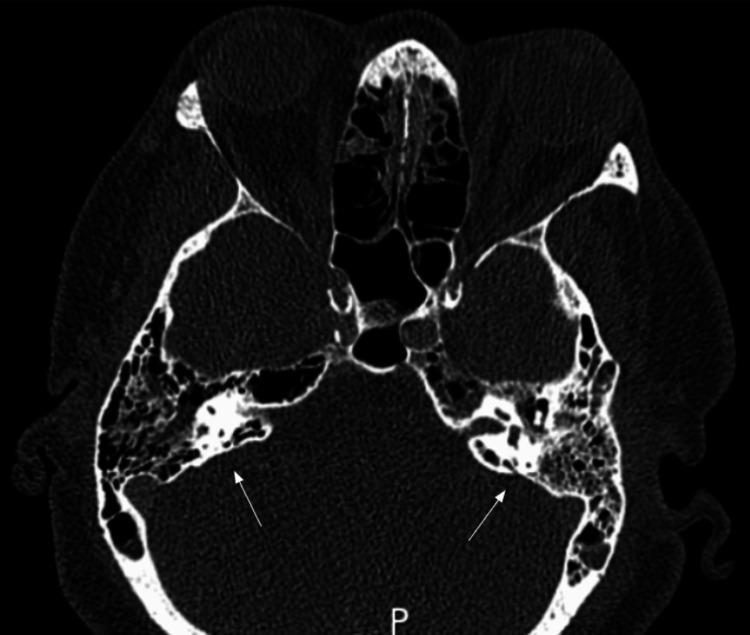

can commonly cause otitis media, sinusitis, pneumonia, or meningitis; however, these infections less frequently can develop into invasive pneumococcal disease (IPD). Vaccination for the prevention of pneumococcal disease has significantly decreased complications from severe infections, including pneumonia, meningitis, and IPD, in patients with certain risk factors. In this case study, we describe a unique presentation of disseminated meningitis and bacteremia in a patient who initially presented with acute otitis media (AOM). Due to the patient's multiple comorbidities of obesity, tobacco use, pre-diabetes, coronary artery disease, and lack of pneumococcal vaccination, their AOM rapidly progressed to life-threatening, an invasive pneumococcal infection which was successfully treated with timely initiation of antibiotics. In addition to discussing the patient's clinical course and treatment regimen, we will review pertinent updates to the pneumococcal vaccination guidelines for high-risk patients and their efficacy in preventing severe disease.

通常可引起中耳炎、鼻窦炎、肺炎或脑膜炎;然而,这些感染较少发展为侵袭性肺炎球菌病(IPD)。预防肺炎球菌病的疫苗接种已显著降低了具有某些危险因素的患者因严重感染(包括肺炎、脑膜炎和IPD)而引发的并发症。在本病例研究中,我们描述了一名最初表现为急性中耳炎(AOM)的患者出现播散性脑膜炎和菌血症的独特病例。由于该患者存在肥胖、吸烟、糖尿病前期、冠状动脉疾病等多种合并症且未接种肺炎球菌疫苗,其AOM迅速进展为危及生命的侵袭性肺炎球菌感染,通过及时使用抗生素成功治愈。除了讨论患者的临床病程和治疗方案外,我们还将回顾高危患者肺炎球菌疫苗接种指南的相关更新及其预防严重疾病的疗效。